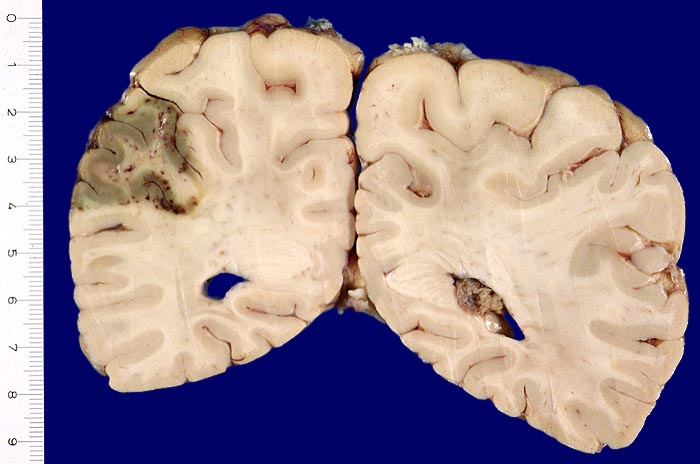

AP/ Anämischer Hirninfarkt

Anämischer Hirninfarkt

Morphologie

Morphologische Merkmale:

• Links unten leptomeningeale Gefässe mit partiell rekanalisierten alten thromboembolischen Verschlüssen.

• Unscharfe Mark-Rindengrenze im Bereich der nekrotischen Rinde.

• Spongiotische Auflockerung der Hirnrinde (hellere Areale).

Makroskopie

Befund

Pathologischer Befund

Normalbefund